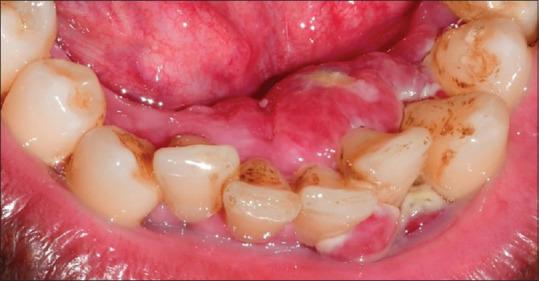

Fibrosarcoma is a rare malignancy of fibroblasts that seldom occurs in the oral cavity. Although rare, fibrosarcoma is an aggressive lesion associated with a poor survival rate. The occurrence of such a highly aggressive lesion on the gingiva is a diagnostic challenge for the clinician. This is because the gingiva is a common site for various inflammatory and nonspecific enlargements, which are commonly benign and the chances to overlook aggressive lesions are high. This case report describes an atypical case of fibrosarcoma of gingiva in a middle-aged individual that mimicked a nonspecific gingival enlargement.

纤维肉瘤是一种罕见的成纤维细胞恶性肿瘤,很少发生于口腔。尽管罕见,但纤维肉瘤是一种侵袭性病变,生存率较低。牙龈出现这种高度侵袭性病变对临床医生来说是一个诊断挑战。这是因为牙龈是各种炎症和非特异性增生的常见部位,这些通常是良性的,因而忽视侵袭性病变的可能性很大。本病例报告描述了一名中年个体牙龈纤维肉瘤的非典型病例,该病例酷似非特异性牙龈增生。